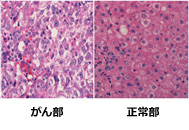

正常な肝臓

肝臓がん

肝臓がんの最終診断は組織検査